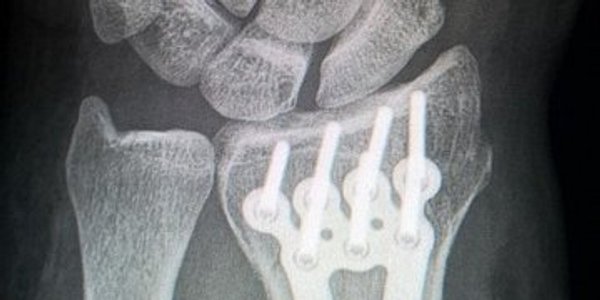

Никаких пластин и винтов. Новый цинковый имплантат может произвести революцию в лечении сложных переломов

Исследователи из университета Монаша совершили прорыв в области лечения переломов костей, разработав уникальный биоразлагаемый материал на основе